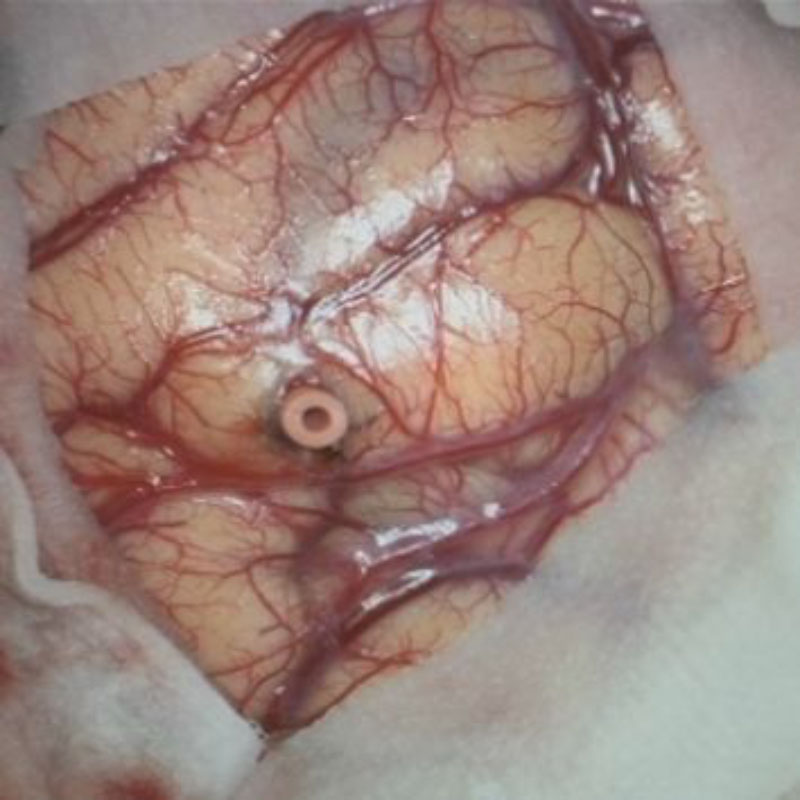

摘出 前